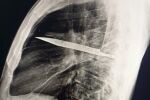

По време на четиричасовата операция в болницата „Кингс Колидж“ професор по неврохирургия Кейумарс Ашкан (MBE) извършил дълбока мозъчна стимулация – хирургична процедура, прилагана при пациенти с двигателни разстройства, устойчиви на лечение, като болестта на Паркинсон – за да имплантира електроди в мозъка на Дениз.

Подкрепян от екип специалисти – невролог, невропсихолог, както и медицински сестри по DBS и операционни сестри – професор Ашкан свързал електродите с генератор на електрически импулси, подобен на пейсмейкър, който подава електрически сигнали, за да промени мозъчната активност и да намали симптомите на Дениз.

„Дълбоката мозъчна стимулация, при която стимулиращи електроди се поставят в дълбоките структури на мозъка, е отдавна утвърдена процедура за подобряване на двигателните симптоми при пациенти с такива разстройства.", разказва професор Ашкан обяснява.

Дениз избрала акумулаторен тип батерия за генератора, имплантиран в гърдите ѝ, която може да издържи до 20 години преди да се наложи подмяна. Устройството подава непрекъснат електрически ток към мозъка ѝ, като иновативният генератор може да следи мозъчната активност и автоматично да регулира стимулацията при нужда.